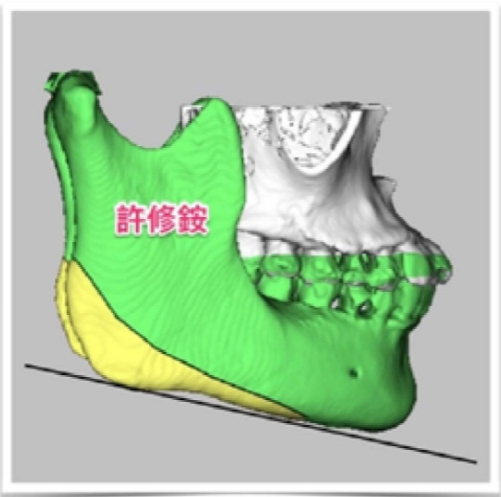

(黃)過度發育之下顎骨角 (黑線)過度平緩下顎下緣

骨頭的切除量依據每個人的需求而有不同。但原則是重新塑造理想的下顎骨角角度以符合美觀(約呈120度),且重新建立下顎平面角(約呈30度),改善下臉部過短的視覺效果。